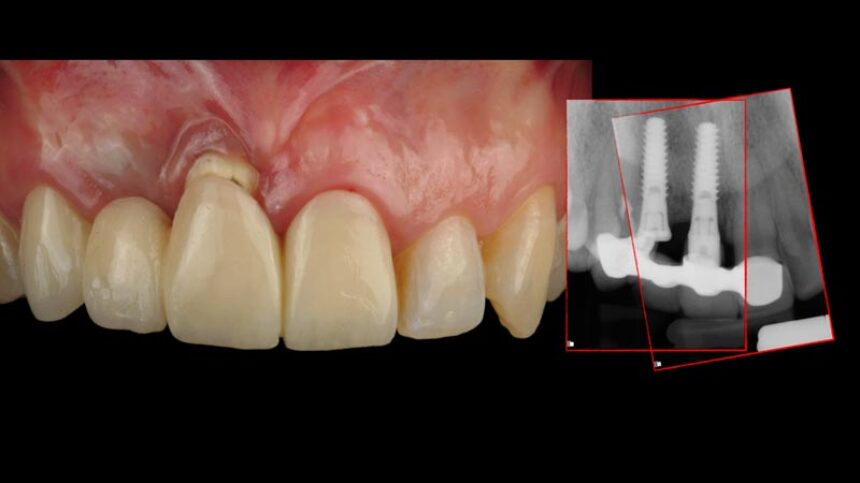

· διαχείριση μαλακών ιστών σε άμεση τοποθέτηση εμφυτεύματος

· επιλογή κατάλληλης χρονικής στιγμής, διαδοχική σειρά βημάτων & επιλογή σημείου

· τεχνική λήψης μοσχεύματος από το έπαρμα της γνάθου, χειρισμός & διαμόρφωση ιστών

· σχέδια συρραφής, επούλωση & spectations